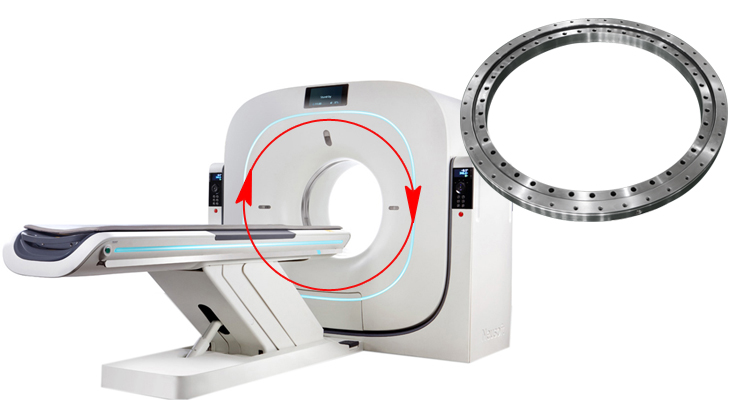

轉盤軸承(回轉支承)在CT機中的應用

在CT機運轉中, X射線管和探測器同時圍繞患者旋轉,這樣可以生成斷面圖,醫生通過它們可以獲得對其診斷有價值的信息。

CT機高速旋轉過程中,為了保證安靜的醫療環境,低噪音和高運行精度的醫療設備回轉支承(轉盤軸承)就顯得及其重要。